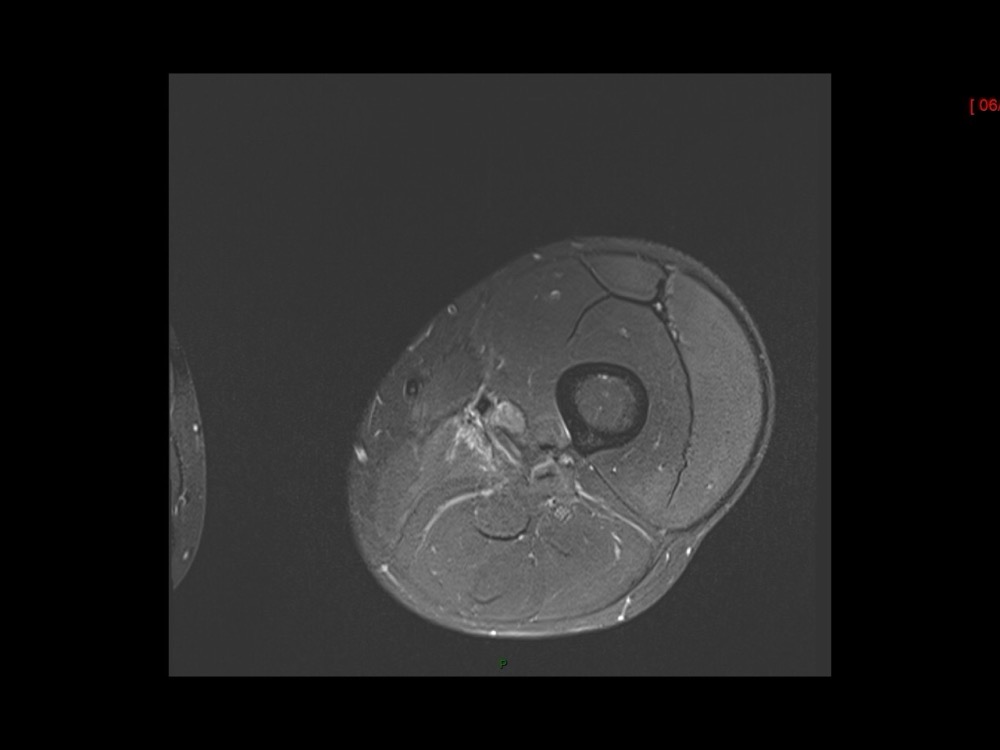

Moalla / Mihoubi-Bouvier / Drapé 18/05/2022